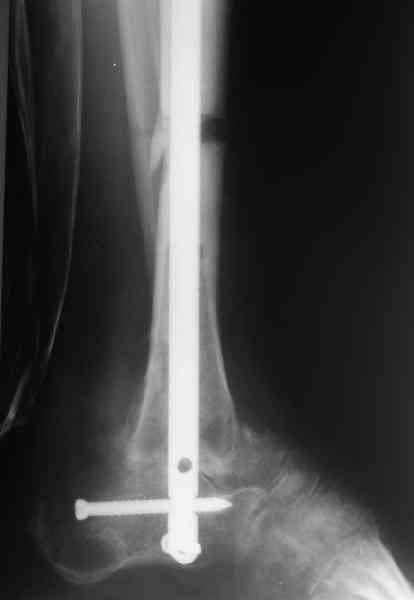

и мы не смогли обещать, что аппарат можно будет совсем скоро снять. Пациент выразил горячее желание расстаться с наружным фиксатором, даже если нужна еще одна операция. На этой неделе выполнили закрытое штифтование (впервые именно в такой ситуации) и сняли аппарат.

Аппарат был снят окончательно только после введения стержня, то есть оставалось по одной спице в проксимальном и дистальном метафизах большеберцовой кости, спицы в пятке. Фото во время рассверливания в приложении.

Стержень 12 мм, винт диаметром 6 мм, костная трубка вокруг хорошая. Перелом такого винта пока не наблюдали ни разу на нескольких сотнях

пациентов.